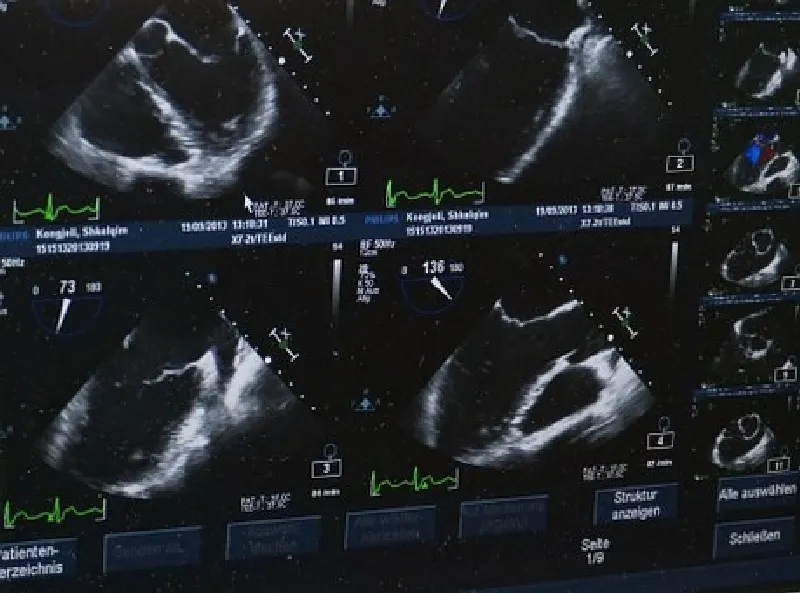

Com a possibilidade de ser alugada com uma empresa de outsourcing de impressão de alta confiabilidade, a impressora de ultrassom proporciona que as imagens deste exame, formadas por meio das ondas sonoras emitidas e captadas durante o processo, sejam impressas em alta qualidade no papel fotográfico, eliminando a necessidade de impressão em filme dry. O processo realizado com a impressora de ultrassom é veloz e permite que o profissional de medicina altere as imagens do exame antes da impressão, melhorando elementos como cor e contraste. Todos estes fatores contribuem para um diagnóstico mais rápido e preciso, o que beneficia o paciente e otimiza o tratamento.